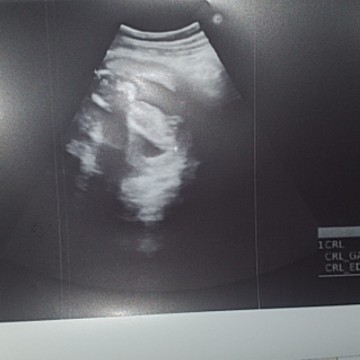

แม่ๆคนไหนอยู่ทีมเดือนไหนกันบ้างค้าา และลูกๆเพศอะไรกันบ้างเอ้ย บ้านนี้ยังไม่รู้เลย.☺️#ท้องแรกคะ #ขอบคุณสำหรับคำตอบค่ะ